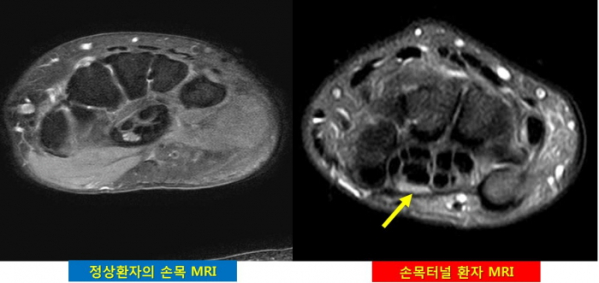

손목터널증후군의 원인은 가사노동처럼 반복적인 손목 사용으로 횡수근 인대가 두꺼워지면서 아래 수근관터널(손목터널)을 누르기 때문이다. 문제는 이 터널 안에는 우리 손의 감각, 움직임을 관장하는 ‘정중신경’이 지난다. 따라서 지속적으로 압박을 받을 경우 신경이 손상된다. 따라서 근육통으로 여기고 파스나 약물/주사 등으로 시간을 허비한다면 손상이 심화되어 수술을 시행하더라도 후유장애 위험을 배제할 수 없다.